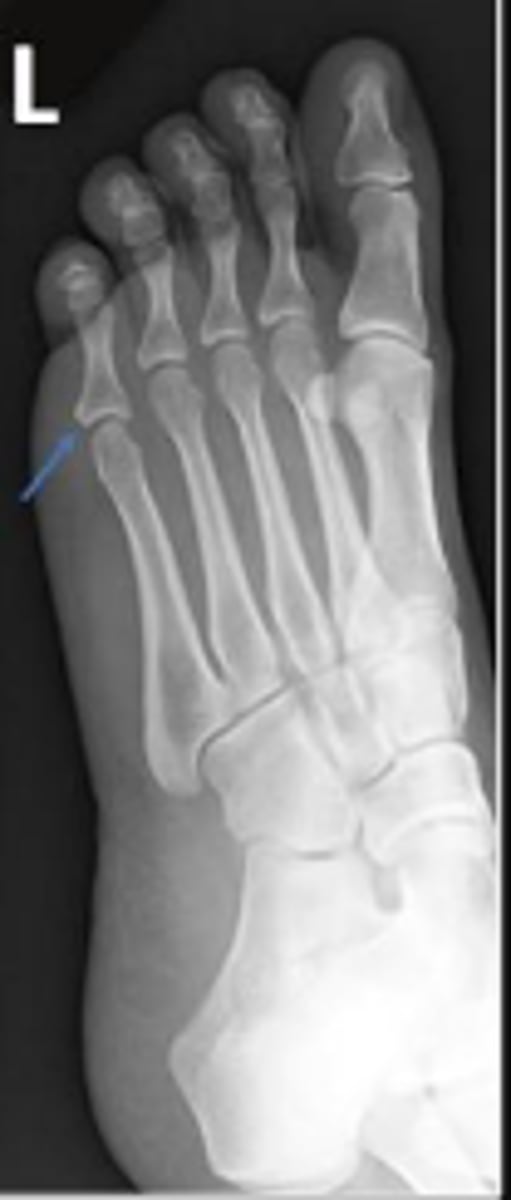

Medial oblique of the left foot

What is the name of the radiographic view?

4th metatarsal

What bone are the arrows pointing t

5th metatarsophalangeal joint of the left foot

What are the arrows pointing to?